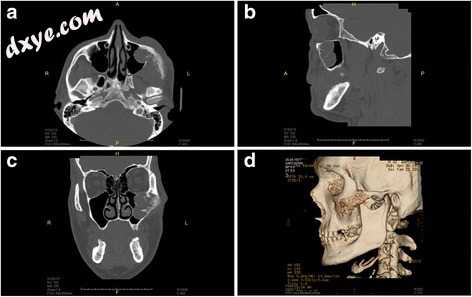

在42岁患者的左中部区域通过组织学证实了基底细胞癌的第三次复发(图1A)。术前CT成像显示肿瘤侵犯上颌窦,眶底和周围软组织,例如面部皮肤,皮下组织和口腔提升肌(图2)。

2.jpg

图2

冠状(a),矢状(b)和轴(c)视图的CT扫描和侧视图中的三维重建(d)